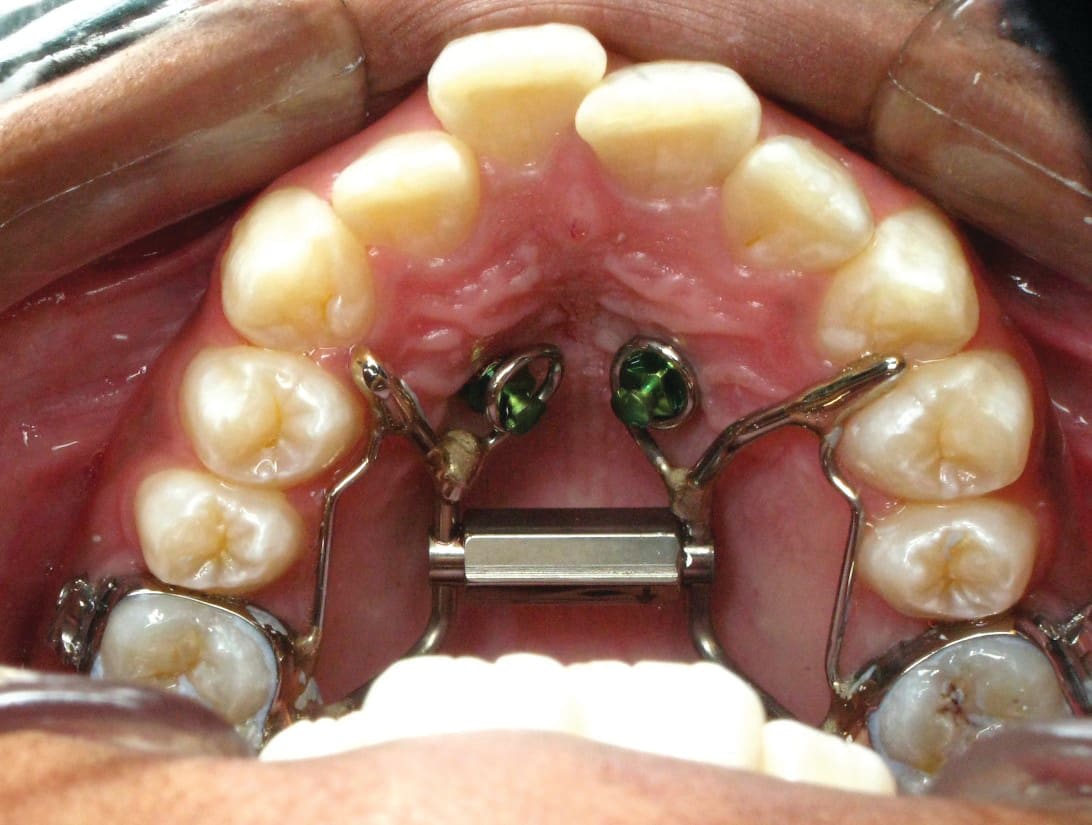

5. Any case that needs expansion of the maxilla. 3D imaging in these cases allow the orthodontist to determine if a cross bite is skeletal or dental. The clinician can readily determine if the molars are inclined in a cross bite or if the entire maxilla is constricted. This in turn can determine what forces are desirable to correct the cross bite. The 3D images also allow the clinician to evaluate the amount of bone around the roots of the teeth that are to be expanded. This also can aid the orthodontist in the type of forces to be utilized. Maybe bone augmentation is indicated in certain areas so as the roots are not once again fenestrated through the cortical bone creating a less stable environment. See Figure 18 through Figure 25. Figure 18 illustrates a maxilla that is constricted due to a narrow maxilla. Figure 19 illustrates the maxilla after expansion. Figure 22 illustrates a molar being tipped lingually. Thus a unilateral cross bite appliance was utilized.